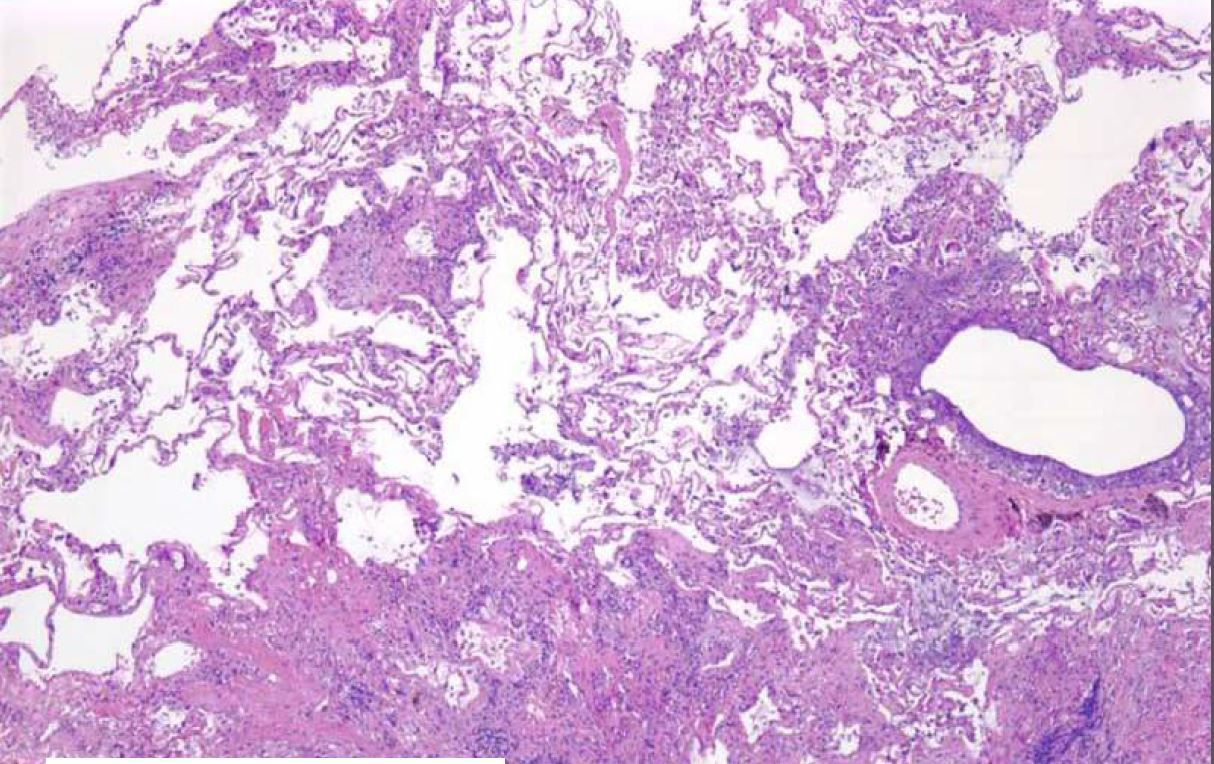

What process is being shown here?

Hallmarks are lower lobes and peripheral/paraseptal

accentuation of changes

UIP